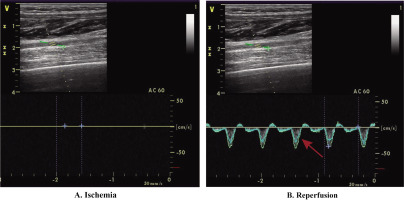

The CON group, serving as the control, received no extra interventions. The TRA group engaged in static stretching and foam rolling. Static stretching targeted the gluteus maximus, quadriceps, and hamstrings on both sides of the body. Each muscle was stretched for 45 seconds, followed by a 15-second rest, and this cycle was repeated three times, resulting in an 18-minute session. After 3 minutes, bilateral foam rolling was simultaneously applied to the gluteus maximus, quadriceps, and hamstrings. Each muscle was massaged for 45 seconds, then rested for 15 seconds, and this was repeated three times for a total of 9 minutes. The total duration of TRA was 30 minutes. In IPC, the ischemic protocol was administered before each ST session, while PEIC underwent the ischemic protocol after each ST. The Doppler ultrasound (LOGIQ E9, General Electric, Boston) was used to closely monitor the IC procedure and arterial inflow to ensure complete closure of the arterial inflow (Fig. 2). All ultrasound procedures were conducted by a physician trained in ultrasound imaging. During the ischemic protocol, participants were lying in a supine position, and non-elastic blood pressure cuffs (Yuwell, China, width: 14 cm) were bilaterally positioned [7] under the gluteal line upper thighs. These cuffs were rapidly inflated to 220 mmHg for 5 minutes to impede arterial inflow. This process was repeated three times, with each compression episode followed by 5 minutes of reperfusion period (cuff release). The intervention protocol, validated for complete occlusion of vascular arterial inflow [17] and induction of physiological responses [18], had a total duration of 30 minutes.